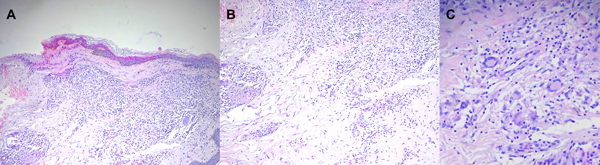

La biopsia de piel mostró a nivel de la dermis granulomas con presencia de una empalizada periférica con macrófagos, células epiteliales y células gigantes multinucleadas, en relación con un proceso crónico granuloatoso (Figura 5).

Figura 5: Anatomía patológica de lesión: En la imagen A se aprecia al topográfico la reacción granulomatosa a nivel de la dermis papilar. (HE 10 x), en la imagen B se confirma la naturaleza inflamatoria granulomatosa, tuberculoide con algunas células gigantes con núcleos en corona o de tipo Langhans. (HE 25x). En la imagen C se puede apreciar las células gigantes tipo Langhans a mayor aumento (40 x).